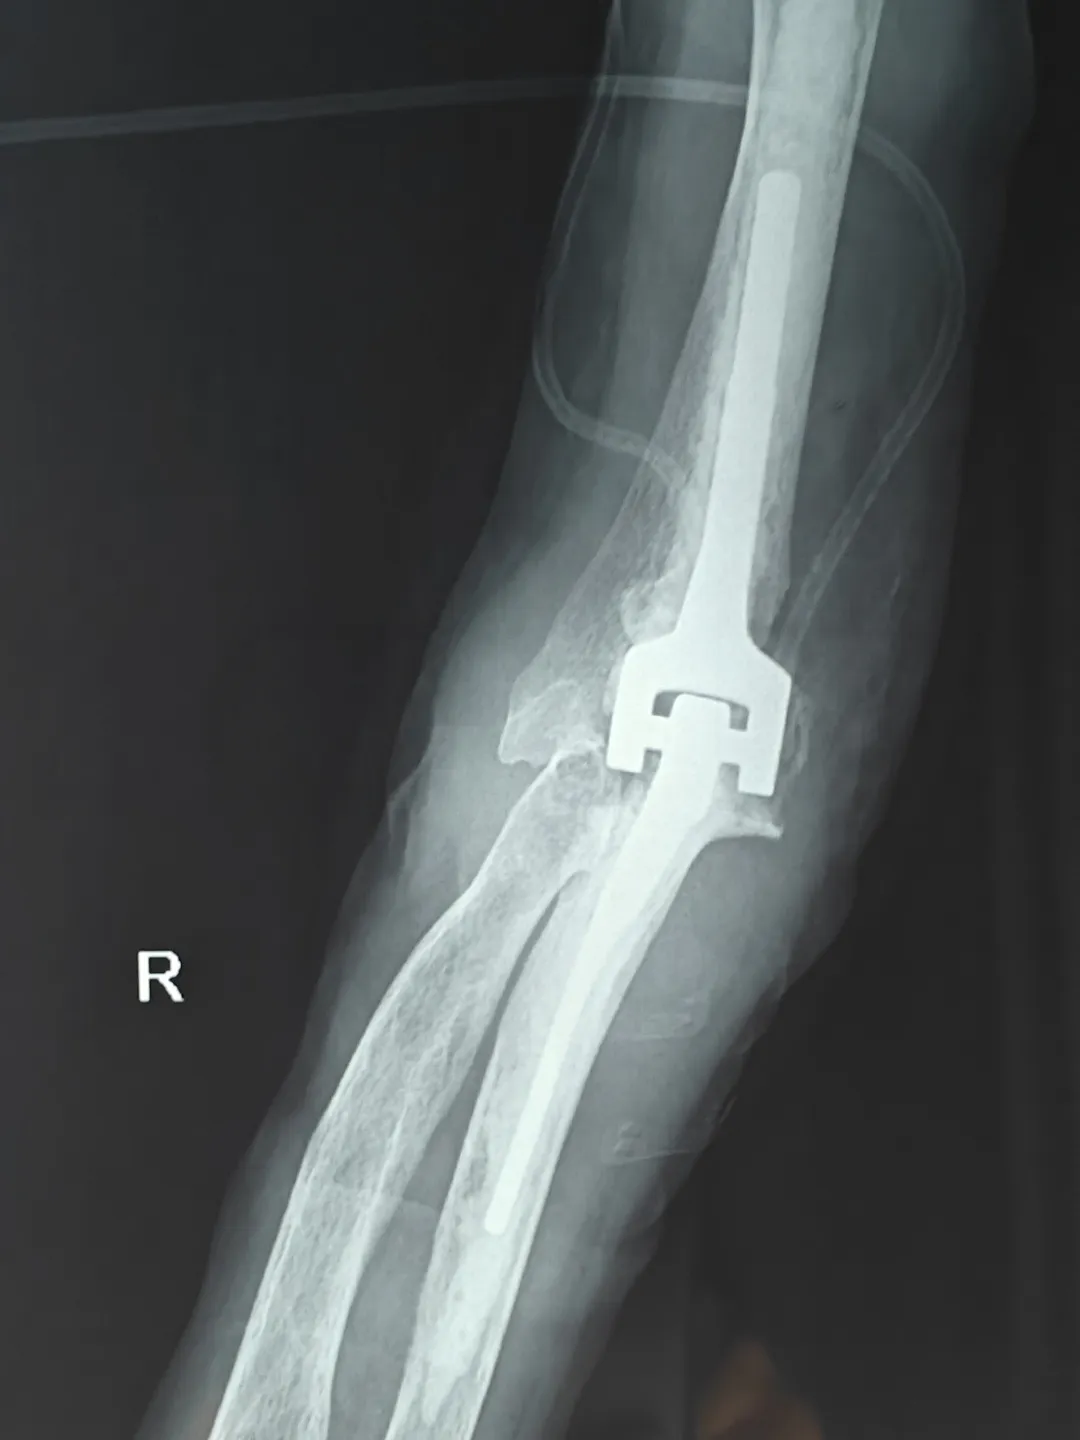

患者术后X光片

北京积水潭医院知名创伤骨科专家李庭教授,作为我院外聘教授,高度重视我院创伤急救外科学科建设,亲临我院进行全肘人工关节置换术的教学手术。整个手术过程行云流水,从细致的术前准备,到精确的手术操作,再到细致的术后管理,体现出李庭教授极高的专业水准和精益求精的手术理念。李庭教授每做一步都会对我院医生详细讲解,将多年的临床经验毫无保留地分享,这种传帮带的学术精神令人敬佩。李庭教授精湛的技术和丰富的经验,为我院创伤急救外科医生团队带来了难得的学习机会,规范了诊治流程,增加了四级手术率,同时也让患者和家属倍感安心。